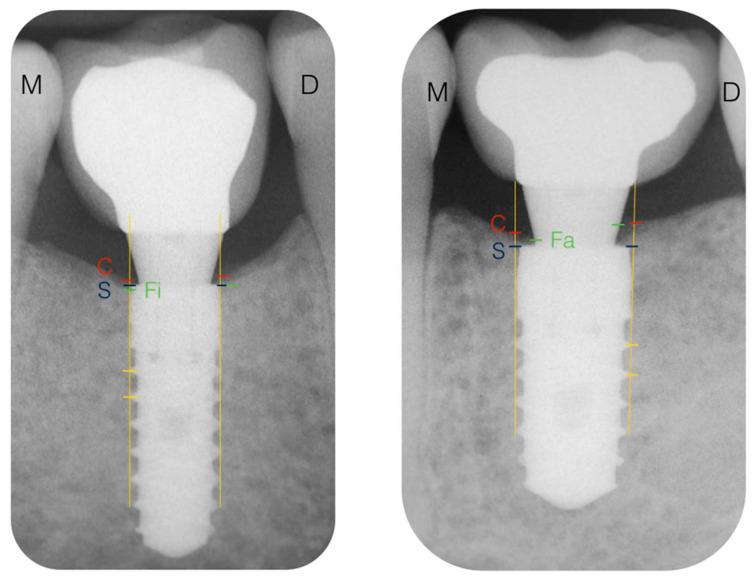

Implant dentistry has evolved over time, resulting in better treatment outcomes for both patients and clinicians. The aim of this trial was to test whether the immediate loading of implants with a platform-switching design influences the marginal bone level, compared to four-week loading, after one year of follow-up. Moreover, a comparison of clinical data regarding implant survival, implant stability, and patient-reported outcome measures (PROMs) was conducted. Klockner VEGA implants with a ContacTi surface were placed in partially edentulous patients in the posterior areas. Group A received an immediately loaded prosthesis (one week) and Group B received an early-loaded prosthesis (four weeks). All abutments were placed at the time of surgery. Radiographic and clinical data were recorded. Twenty-one patients were treated (35 implants). No implants were lost during the study. The final marginal bone level did not show differences between groups. The bone loss at 12 months at the implant level was 0.00 mm for both groups (median). The final implant quotient stability (ISQ) values did not differ between groups (median 73 and 70.25), nor did the other clinical parameters or PROMs. : The results suggest that neither of the loading protocols with the implants used influenced the marginal bone level-not the osseointegration rate, clinical conditions, or PROMs.

种植体牙科随着时间的推移而发展,为患者和临床医生带来了更好的治疗效果。本试验的目的是测试在一年的随访后,与四星期负重相比,平台转换设计的种植体即刻负重是否会影响边缘骨水平。此外,还对有关种植体存活率、种植体稳定性和患者报告的结果测量(PROMs)的临床数据进行了比较。Klockner VEGA 种植体采用 ContacTi 表面,植入在后牙区的部分缺牙患者中。A 组接受即刻负重修复体(一周),B 组接受早期负重修复体(四周)。所有基台均在手术时放置。记录放射学和临床数据。21 名患者接受了治疗(35 个种植体)。研究过程中没有种植体丢失。两组的最终边缘骨水平没有差异。两组的种植体水平 12 个月时的骨损失均为 0.00 毫米(中位数)。两组的最终种植体商稳定(ISQ)值没有差异(中位数分别为 73 和 70.25),其他临床参数和 PROMs 也没有差异。结果表明,使用的两种种植体负重方案均未影响边缘骨水平,即骨整合率、临床状况或 PROMs 不受影响。